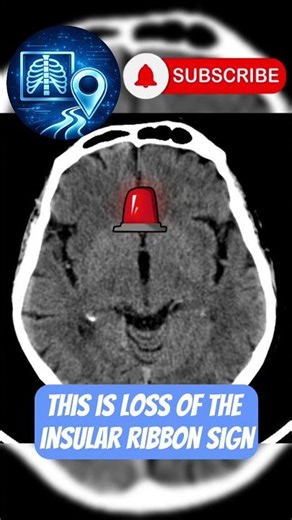

- Right MCA

Stroke - Reticular